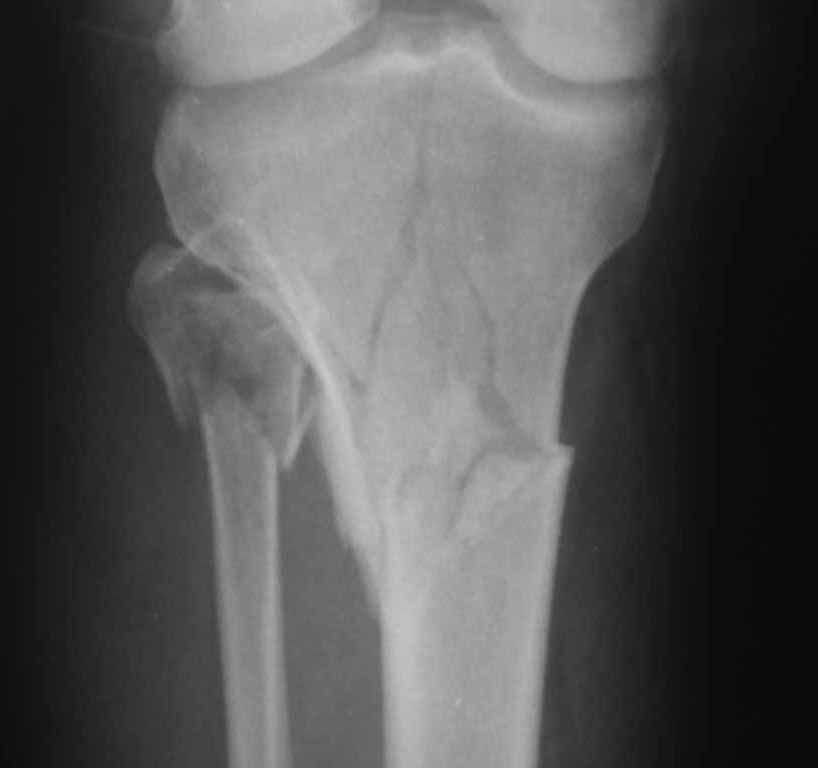

Подскажите пожалуйста, какой фиксатор подойдет для данного

перелома. Мужчина 40 лет получил закрытый внутрисуставной перелом верхней трети костей

правой голени в результате ДТП (см. рентгенограммы). Какой фиксатор подошел бы для данного

перелома понятно, однако у пациента имеется по передне-наружной поверхности верхней трети

голени ссадина и участок некроза кожных покровов (см. фото), поэтому латеральная

мыщелковая пластина не подойдет, а медиальных пластин у фирм-производителей нет. Пациент